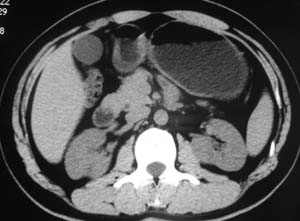

以下是引用子期在2010-3-19 20:47:00的发言:[br]血管畸形的ct增强应该有明显强化,本例并不相符合。本例双肾局部的略低密度影,累及肾盂,局部皮质明显变薄、内陷,增强扫描有轻度的强化,应考虑为炎性病变,患者为年轻男性,累及双肾的感染以结核较常见,可以没有明显的临床症状,尿中有时候也并不能查出什么;肾脓肿常有明显感染中毒症状,本例不符,另外一般的肾盂肾炎或肾小球肾炎通过小便就可确诊,其它还不能排除的是黄色肉芽肿性肾盂肾炎,然而单凭ct一般也很难鉴别。